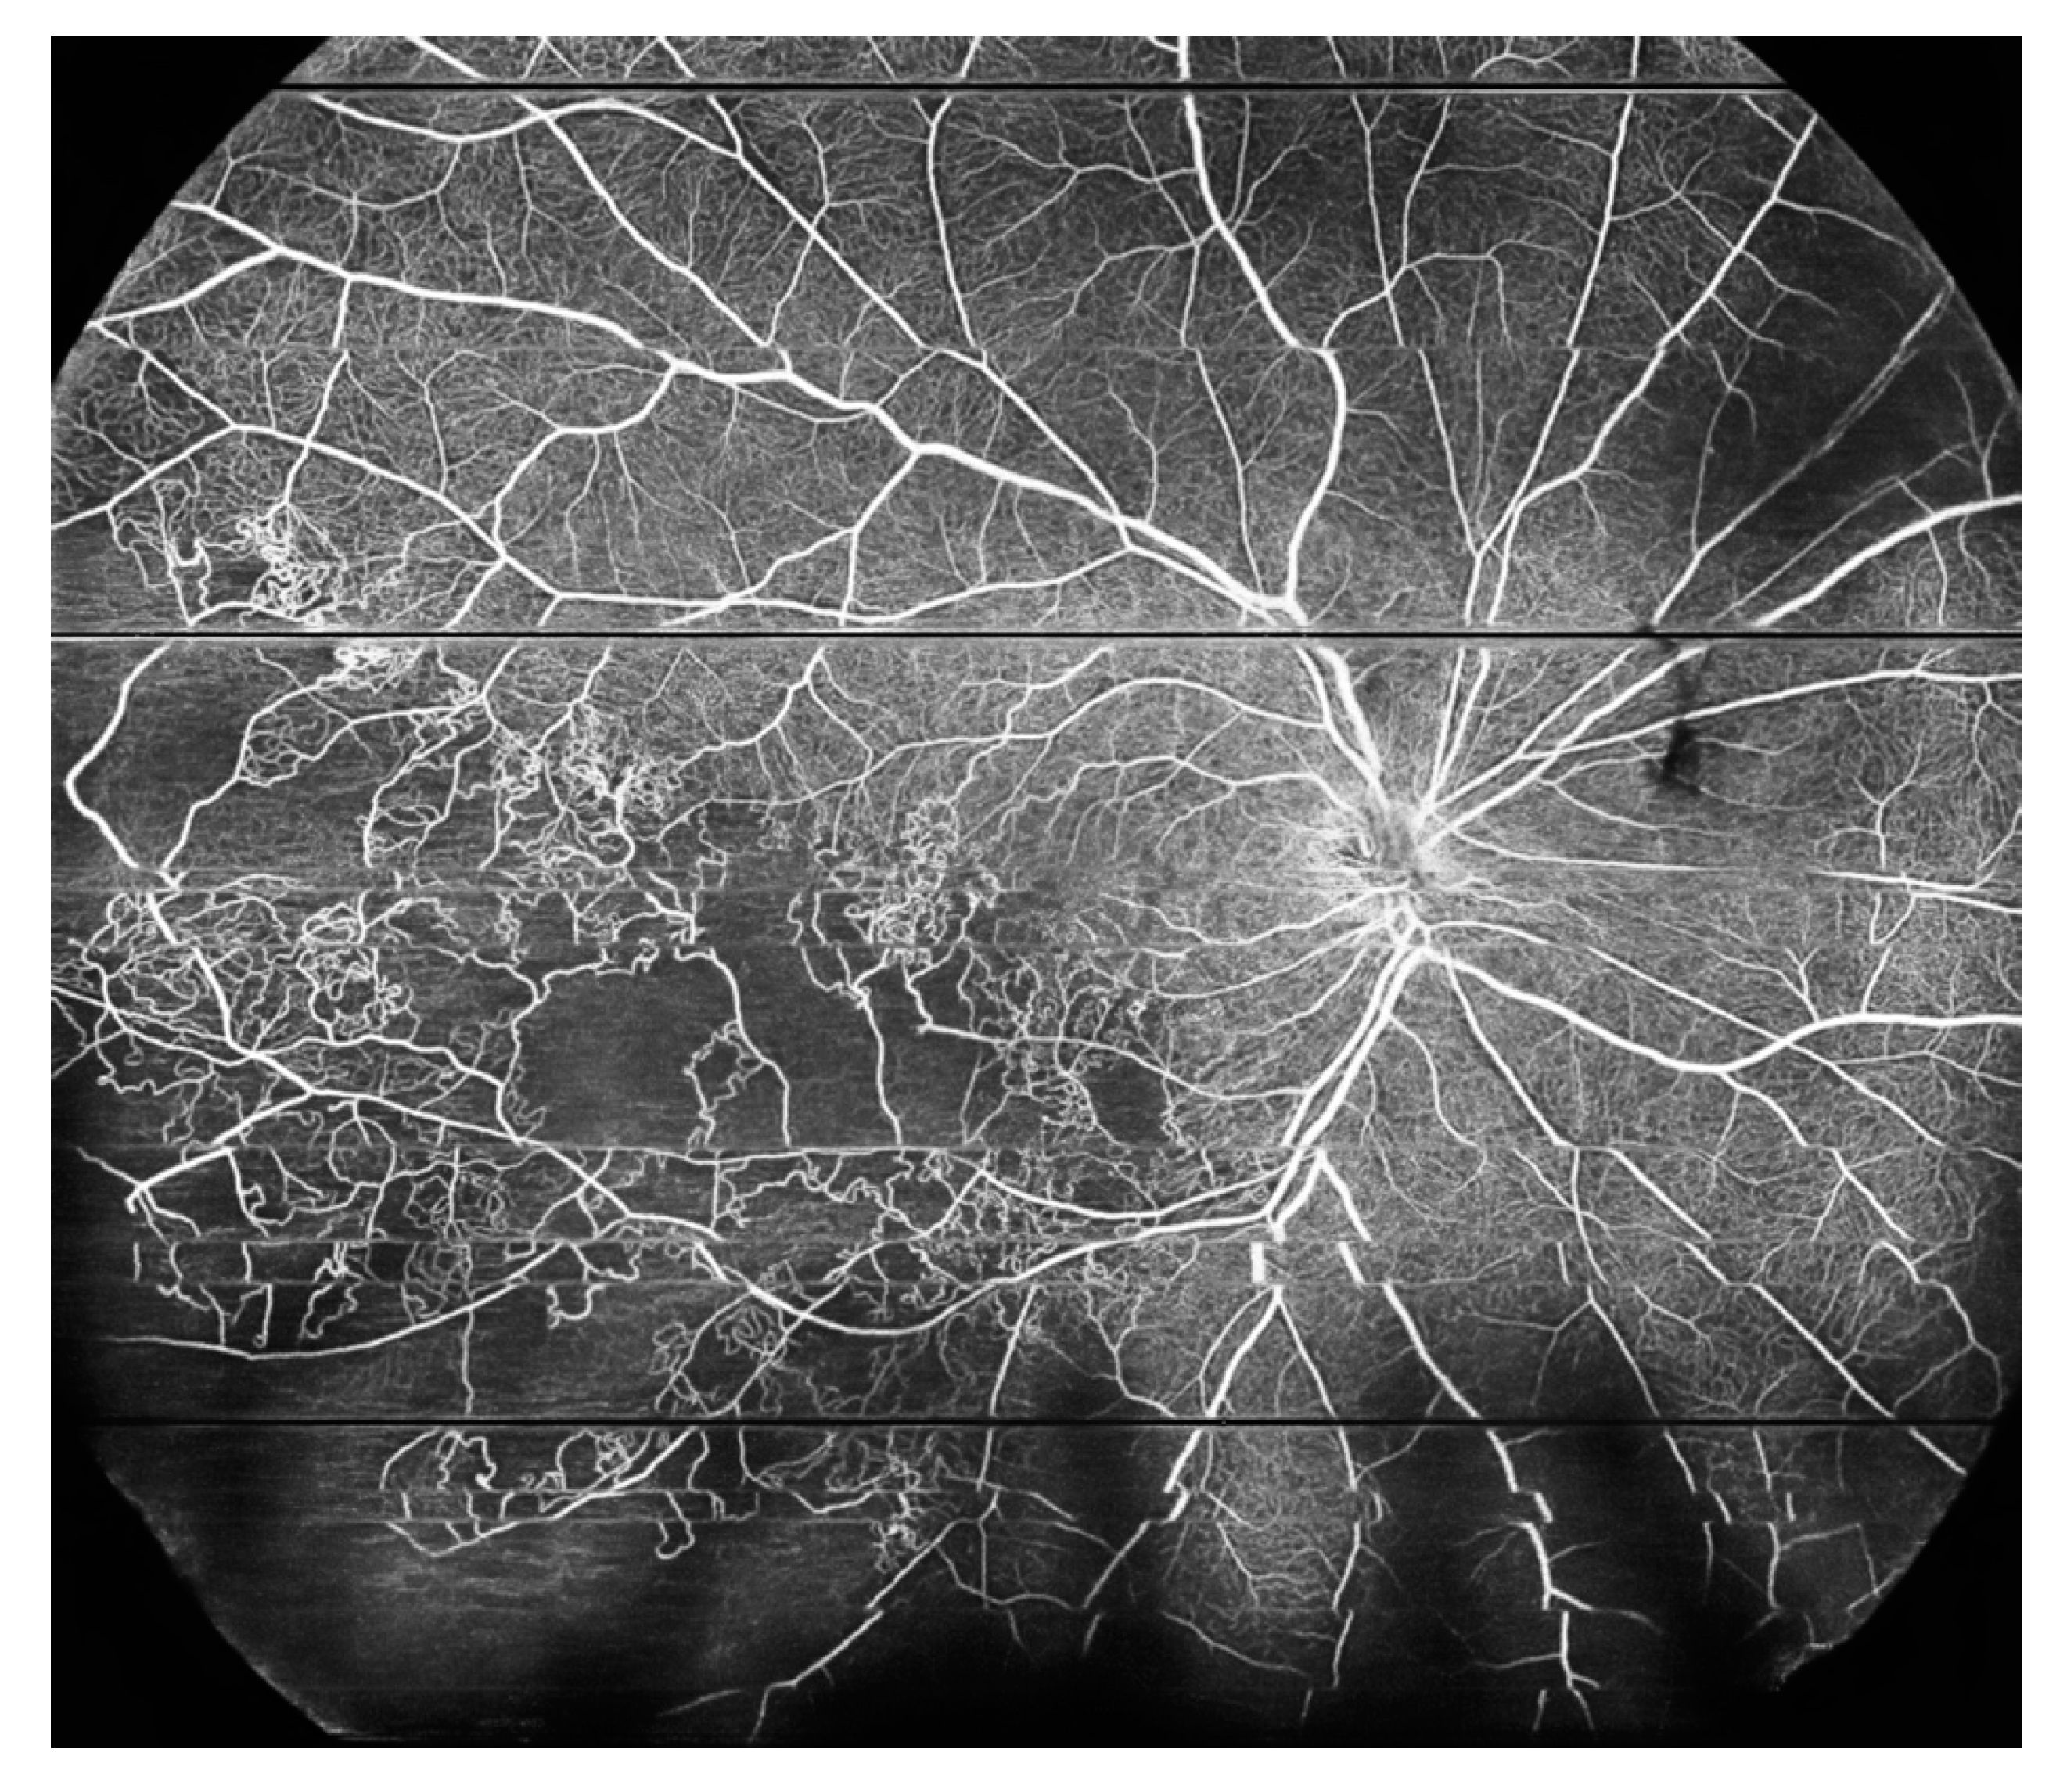

| Picchi et al. 2020 [20] | UWF-FA Optos® 200Tx versus OCTA with 12 × 12 mm fields of five visual fixations using the PLEX Elite 9000® | 82 eyes; NV detection in PDR patients | NVD was detected in 13 eyes by UWF-CP, 35 eyes by UWF-FA, and 37 eyes by WF-OCTA. Upon review of the 2500 OCT B-scans with superimposed flow overlay, NVD was confirmed in 37 eyes. UWF-CP analysis detected 62 foci of NVE out of the 196 confirmed by B-scan (31.6% detection rate). An additional 11 foci of NVE seen on UWF-CP were not confirmed by B-Scan (15% false positive rate). UWF-FA identified 182 foci of NVE (detection rate 91.3%); WF-OCTA detected 196 NVE (detection rate 100%). The rate of false positives for both UWF-FA and WF-OCTA was < 2%. Respectively, the sensitivity and specificity of NVD detection were 35.1% and 97.8% for UWF-CP, 94.6% and 100% for UWF-FA, and 100% and 100% for WF-OCTA. |